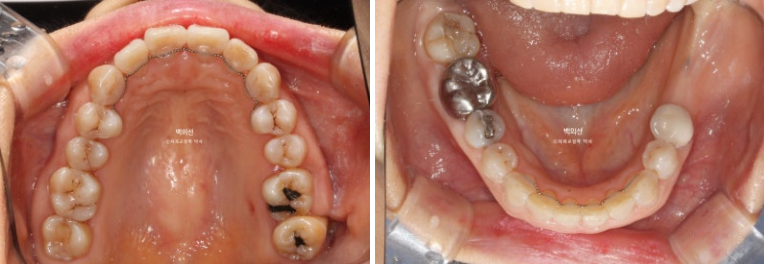

좌측 아래는 어금니가 빠진 지 오래된 상태입니다.

임플란트가 필요한 부분을 장기간 방치하면 대합치가 조금씩 솟아 내려오게 됩니다.

파란화살표 임플란트를 해넣기 위해서는 교정으로 내려온 대합치를 합입 시켜 올려야 합니다.

특히 내려온 큰어금니들 중 맨 뒤 제2대구치는 살릴 수 없어 타병원에서 발치진단이 나온 상태입니다.

잇몸이 뿌리끝까지 내려가 상태가 좋지 않습니다.

다른 문제가 하나 더 있습니다. 파란 화살표 치아는 신경치료 된 치아인데 뿌리끝에 염증이 있습니다.

이 치아 역시 타병원에서 쓸때까지 쓰다가 문제 생기면 발치 후 임플란트 하는 걸로 알고 계셨습니다.

인비절라인이 이와같이 치근단 염증이 있거나 잇몸이 약해 교정력이 가해지지 않아야할 치아들이 있는 경우 큰 장점이 있습니다.

치료의 처음부터 끝까지 치아이동이 없게끔 치료계획을 세우면, 약간 치아에 무리가 가지 않게 나머지 타겟치아들만 움직이면서 교정이 가능합니다.